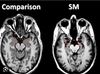

Qu'est qui est arrivé à Phineas Gage?

Barre de fer à travers le cortex orbitofrontal A survécu pendant 12 ans sans trop de séquelles médicales - Changement brutal de la personnalité (sphère affective): - Puéril, Désinhibé, Impulsif (irresponsable) - Détachement des émotions (dissociation cognitivo-affective) - Jugement social inapproprié